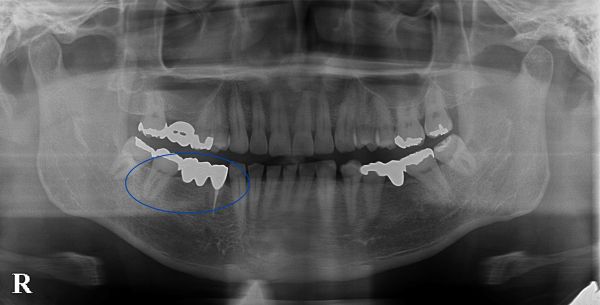

こちらがその時のレントゲン写真になります。

右下4番目と7番目の歯でブリッジが入っておりました。右下4番目の歯の周囲に薄く骨が溶けている像が見られました。

歯根破折(根のヒビ)を疑いましたが、マイクロスコープを用いても歯根破折を確認できなかったため、再根管治療(根の治療のやり直し)を行い、しばらく経過を見ました。

数ヶ月後のメインテナンス時にレントゲン写真を撮影したところ、周囲の歯の骨の吸収が進んでいることが分かりました。